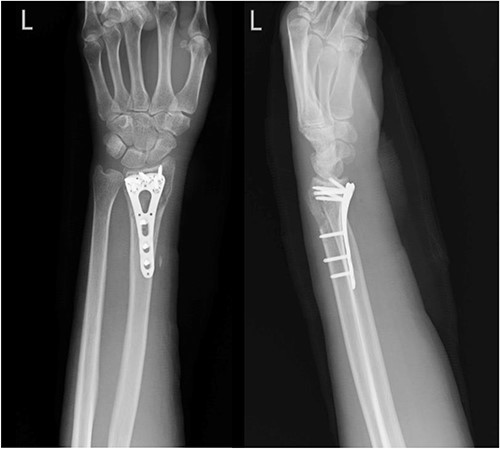

A 68-year-old female with underlying diseases of dyslipidemia, hypertension and a history of left distal radial fracture status post open reduction internal fixation on 4 April 2021, presented to our plastic surgery OPD on October 2022 with complaints of limited left thumb flexion for the past month. She reported experiencing sudden pain in her left forearm and left wrist radial site while pulling grass at home. On examination, she was found to have poor flexion of the left thumb, which was suggestive of a rupture of the FPL tendon. Left wrist X-ray showed fracture over radius with compression plate fixation (Fig. 3). After thorough discussion with the patient, it was decided that she would undergo tendon repair surgery.

Left wrist X-ray showing a fracture over the radius with compression plate fixation.